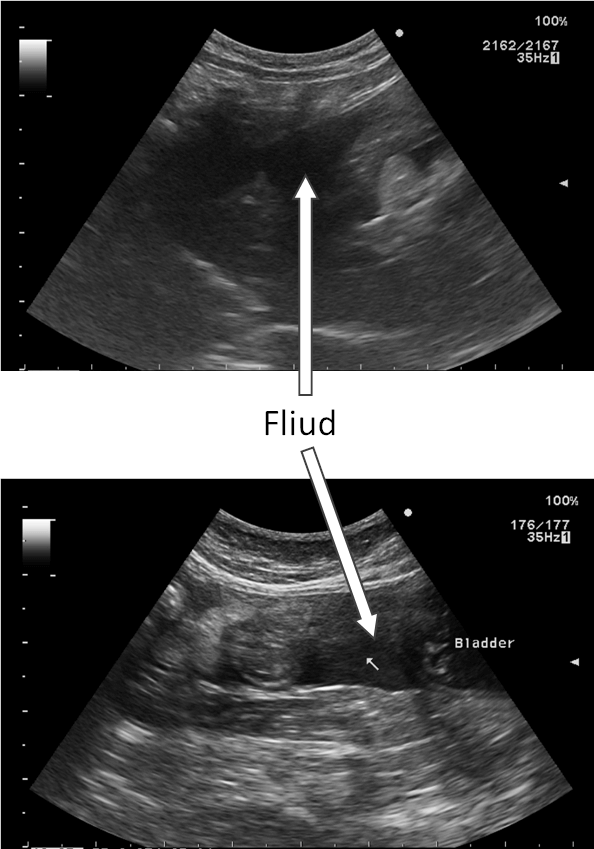

腹部超音波検査

― 右上腹部に40mm大の腫瘤陰影

― 腹腔内に液体貯留

― 穿刺吸引→血様の液体